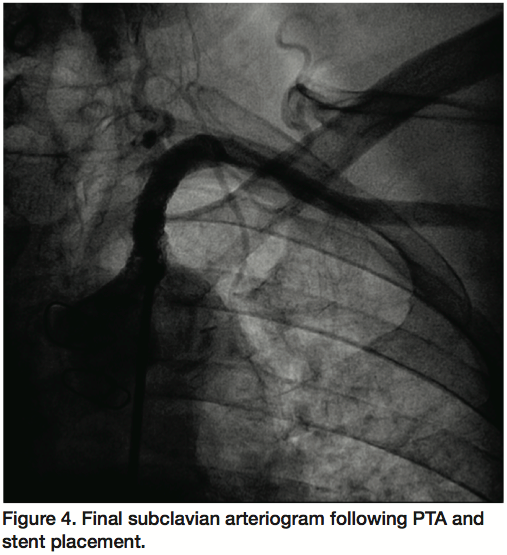

A 6 Fr, 65 cm sheath (Terumo Corporation, Tokyo, Japan) was used to engage the origin of the left subclavian artery via the right femoral artery. Unfractionated heparin anticoagulation was used during the procedure. A V18 Control Wire guidewire (Boston Scientific) crossed the severely calcified, eccentric lesion in the subclavian artery. An AngioSculpt 4 x 40 mm scoring balloon catheter (AngioScore) was used for predilatation given the calcific burden of the lesion (12 atm, 40 seconds) (Figure 2). The V18 guidewire was then exchanged for a Supra Core 0.035 guidewire (Abbott Vascular) over which a subsequent predilatation was performed with a 5 x 40 mm FoxCross balloon (Abbott) (9 atm, 30 seconds). An Express LD 8 x 27 mm balloon-expandable stent (Boston Scientific) was deployed (10 atm, 20 seconds) (Figure 3) and postdilatation was performed with a 9 x 20 mm Admiral Xtreme balloon (Invatec, Medtronic, 9 atm, 20 seconds). An excellent angiographic result was achieved (Figure 4) with minimal residual left subclavian stenosis and no gradient across the lesion. In addition, at the end of the procedure there was angiographic evidence of antegrade left vertebral artery flow and more brisk filling of the LIMA. The patient’s symptoms of angina and left upper extremity claudication resolved and he remained symptom-free at his 6-month follow-up interview.